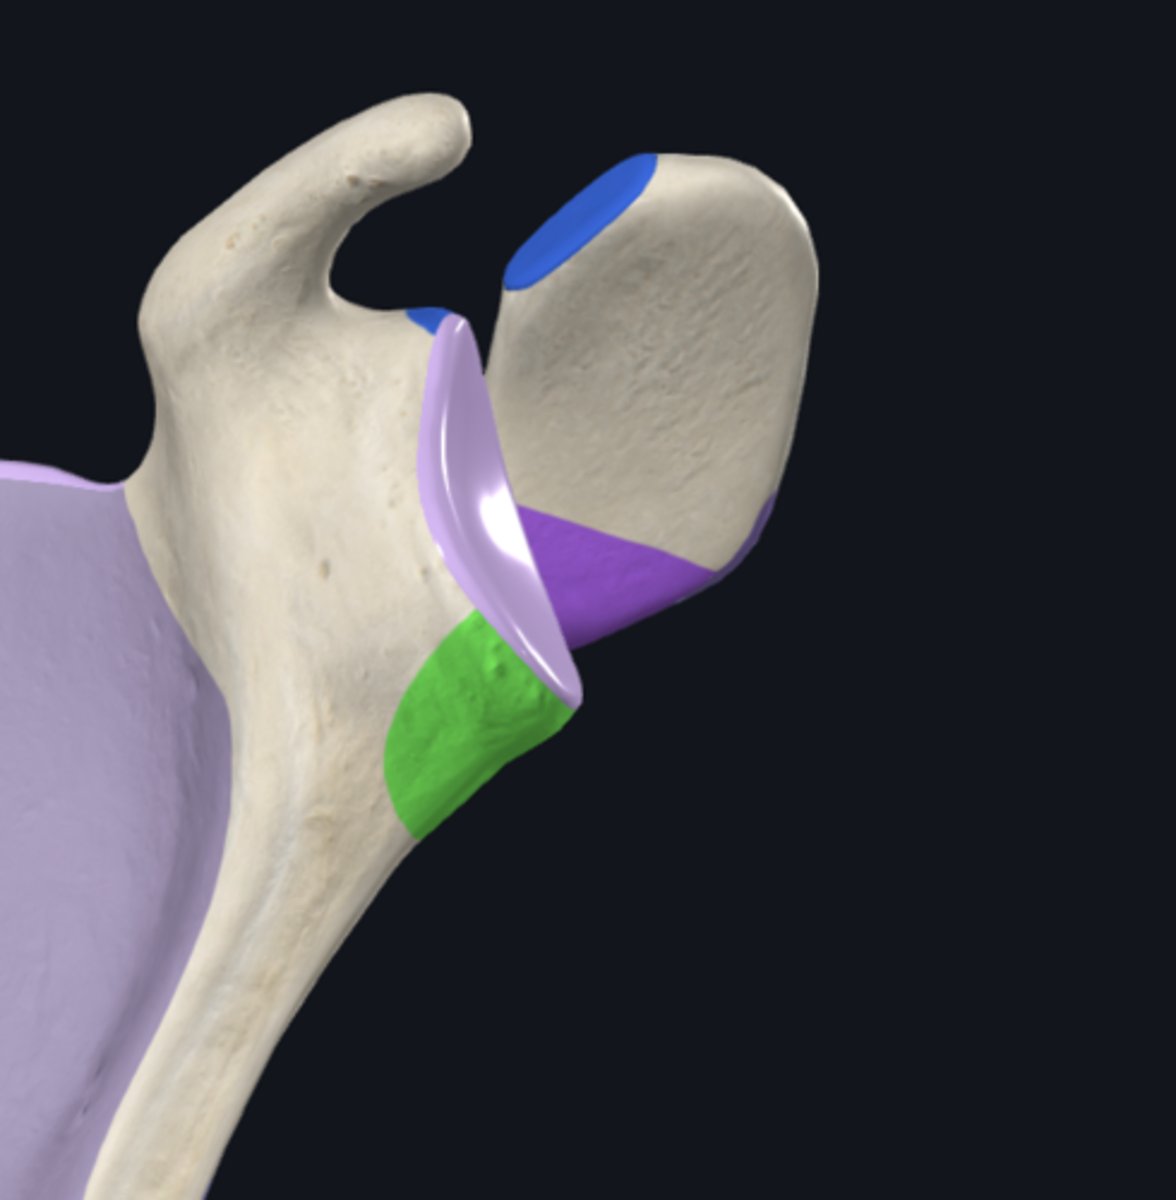

Acromion

Coracoid process

scapular notch

acromial angle

clavicular facet

glenoid fossa

infraglenoid tubercle

supraglenoid notch

supraglenoid tubercle